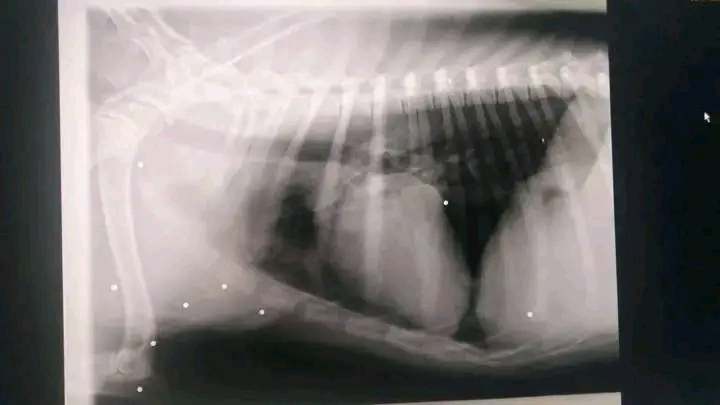

Pensavo fosse stato investito, invece in clinica si è scoperto che è stato sparato, forse oggetto di qualche cretino inqualificabile che aveva voglia di divertirsi con un povero essere indifeso. Aveva praticamente proiettili ovunque…!!!

Pensate che un proiettile l’ha colpito anche ai testicoli, e provava un dolore disumano. E’ stato operato d’urgenza ed è sulla via della guarigione. Posso dire che sta meglio …e che non è più in pericolo di vita.